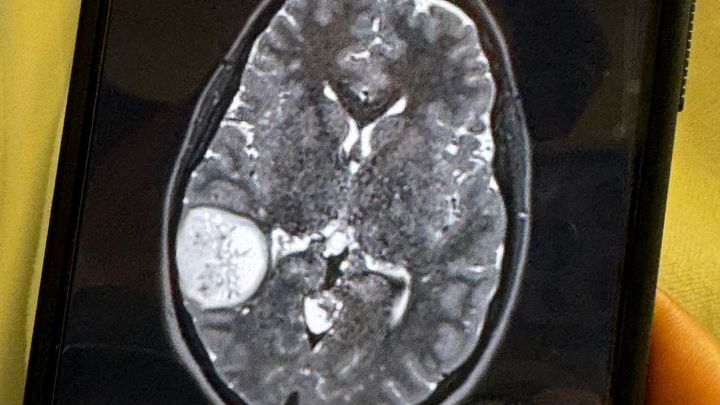

As most of you know Farrah underwent surgery in February due to a severe brain tumor that caused a seizure and resulted in a motor vehicle accident. Therefore she has no car and is not able to drive or work for a long time now. She has completed her first round of chemotherapy and radiation that consisted of going to Austin everyday Monday-Friday for 3 months. To prepare for further and more aggressive chemotherapy she just had surgery on August 21st to have a port placed where the chemo will be injected a few times a month along with labs that have to be done weekly in austin and Harker Heights. The cancer has not come back nor spread but with the type that she has they say will never be completely gone and has to be kept stable. Subjectively because of her medical condition and concurrent chemo and radiation treatments she suffers from: seizures, headaches, difficulty with word finding, weakness in the right side, forgetful, distracted, decreased focus, nausea, irritability, fatigue and hairloss. Her activities are limited because she is not suppose to drive, has difficulty time maintaining a consistent schedule. Again not able to work so can use all the help possible with daily responsibilities and or expenses. Thanks for all the prayers and support here on out

Farrah Carnes is a single mother of three grade school girls and a resident of Lampasas, Tx, she is now at home recovering from a severe brain tumor that they found after a car accident that totaled her car. Farrah had a seizure Friday 2/9/24 (Her birthday to be exact) which caused a car accident! She was then rushed to seton in Harker Heights where they did a CT SCAN and MRI which showed a mass/tumor on the right side of her brain! They transferred her to Seaton medical center in Round Rock where they have a neurosurgeon and better team! They have decided instead of just doing a biopsy which would only be taking part of it at the time and could just cause spreading and bleeding that they are actually going in to remove as much as they can to also send off to see what and if she will need radiation and/or chemo! Surgery has went well and the doctors believe to have removed the tumor in its entirety but aren’t sure if it’s cancerous or not yet. She has begun recovery very well and is able to talk and walk with the help of a walker so today 2/15/24 the doctors have released her to go home. Farrah is going to need extended supervision and will not be able to drive on her own for about 6 months. She is very grateful for everything anyone can help with as she continues on this long road of recovery. Thank you to everyone in advance!!